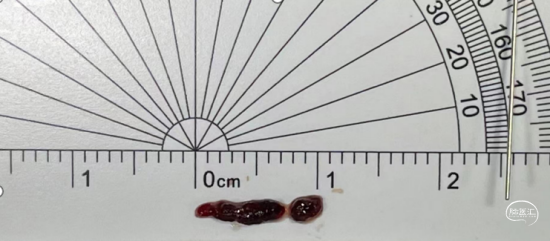

体外可见支架内及Tethys®中间导引导管内血栓取出